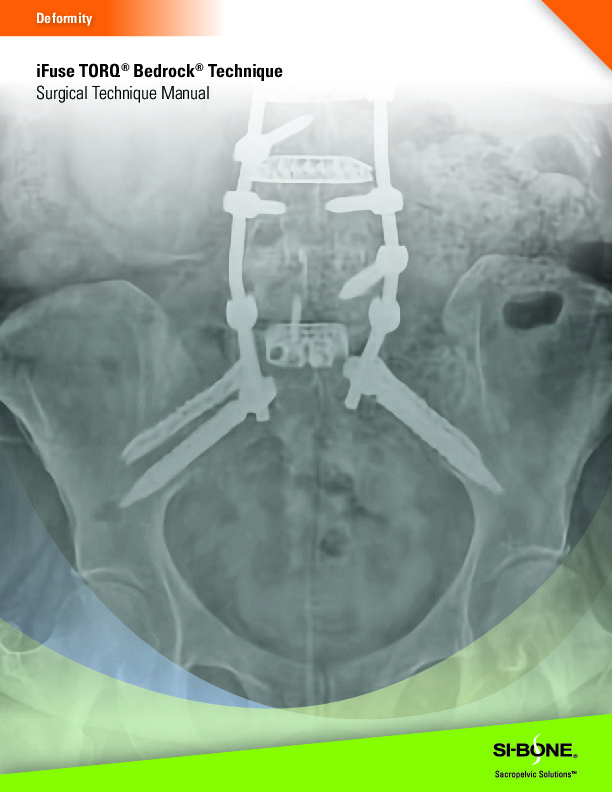

The iFuse TORQ by SI-Bone is a 3D printed titanium screw for use in the fusion and stabilization of the sacroiliac joint. It features a porous open architecture utilizing FuSIon 3D Surface Printed Porous Lattice which allows for osseous integration.